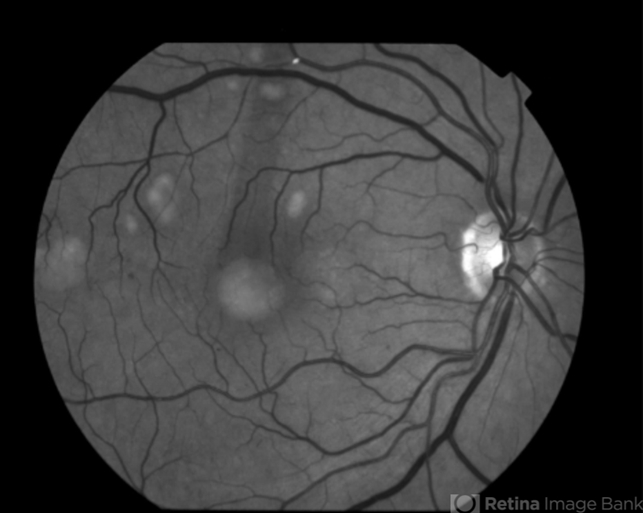

Multifocal Best Disease

Best disease, adult vitelliform dystrophy

Fundus camera

Macular exam reveals yellow subretinal pigment clumping in each macula, including the foveal area.